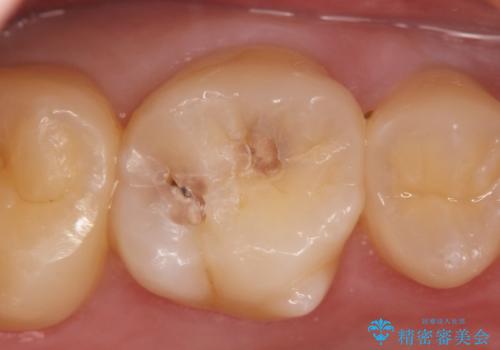

虫歯は放置すると大きくなり、神経まで達し根管治療が必要になったり抜歯に至ることもある進行性の病気です。

早期の発見・治療をすることで期間も費用も少なくすることができます。